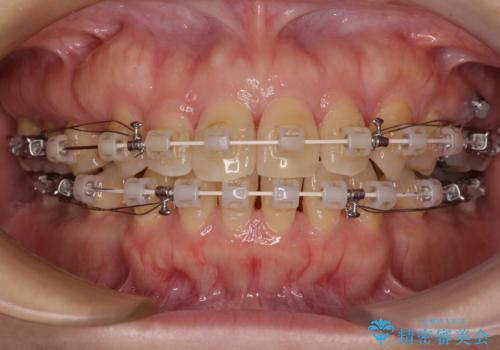

- 矯正装置

- 審美装置

- 前歯のデコボコと口元の突出感を気にして来院された患者様です。

上下前歯がくちばしのように突出していたため、上下左右の第一小臼歯4本を抜歯し、ワイヤー装置にて矯正治療を行うこととしました。

上顎骨に対して下顎骨がやや前方位に位置しているため、歯肉退縮を回避するために下顎前歯をあまり内側に移動させることができない状況でしたが、十分に口元の突出感を改善することができました。